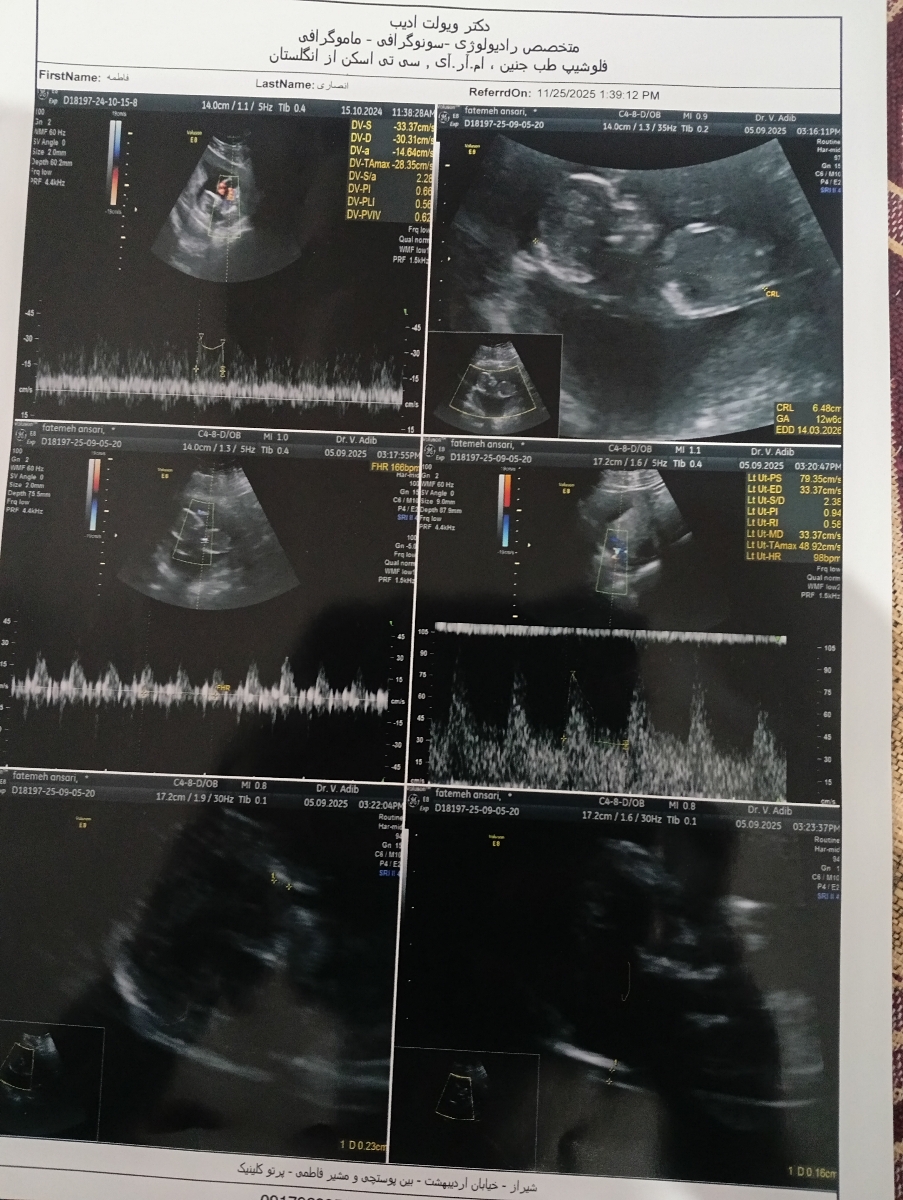

سلام به روی ماهتون مامان جان

سونوگرافی هیچ مشکلی ندارد مبارکتان باشد درمورد غربالگری جان دلم ، ریسک محاسبه شده برای تریزومی ۱۸ و 13 در محدوده کم خطر قرار دارد اما در مورد تریزومی 21 یعنی سندروم داون، ریسک محاسبه شده اگرچه مثبت و پرخطر نیست، اما در محدوده حد وسط قرار دارد. به بیانی اگر 1190 خانم و مادر باردار مشابه به شرایط شما باشند، فرزند یک نفر از بیمار و فرزند مابقی سالم است. اگرچه این رقم به نظر ناچیز است اما در علم پزشکی و باتوجه به اینکه بیماری داون درمان پذیر نیست، اهمیت بسیار زیادی دارد و بنابراين در صورت صلاحدید پزشکتان باید بررسی های تکمیلی انجام شوند تا مطمئن شویم که کوچولوی شما سالم است. بهتر است سل فری دی ان ای یا همان nipt انجام شود و یا غربالگری مرحله دوم را به شیوه سکوئنشنوال در همان آزمایشگاه قبلی که مرحله اول انجام شده، انجام شود. تصمیم گیری نهایی در مورد نوع بررسی مورد نیاز با پزشک شما است ولی باتوجه به سطح مارکر بتا توصیه من سل فری دی ان ای هست. همچنین با پزشک خود در مورد دریافت آسپرین مشورت کرده و در سه ماهه دوم بارداری سونوگرافی کالرداپلر عروق جفتی انجام دهید تا خیالمان از هر جهت راحت شود 💞